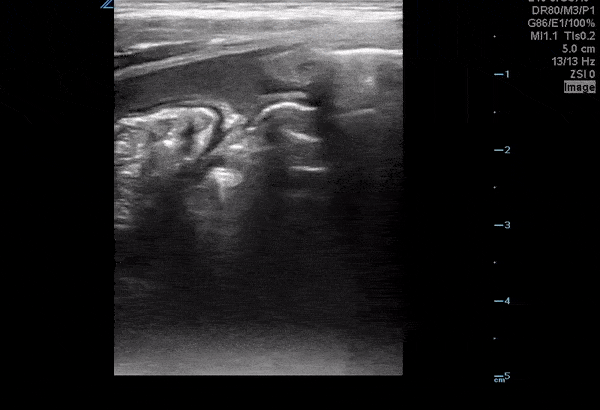

Bowel-GI - Ruptured Appendicitis with Intraabdominal Free Fluid

A 3 year old M presented with 3 days of fever, vomiting and abdominal pain. He was lethargic on arrival and found to be septic. POCUS shows ruptured appendicitis with a significant amount of hypoechoic fluid in the abdomen. Paul Khalil, MD. Assistant PEM POCUS director at University of Louisville/Norton Children’s @khalil3paul